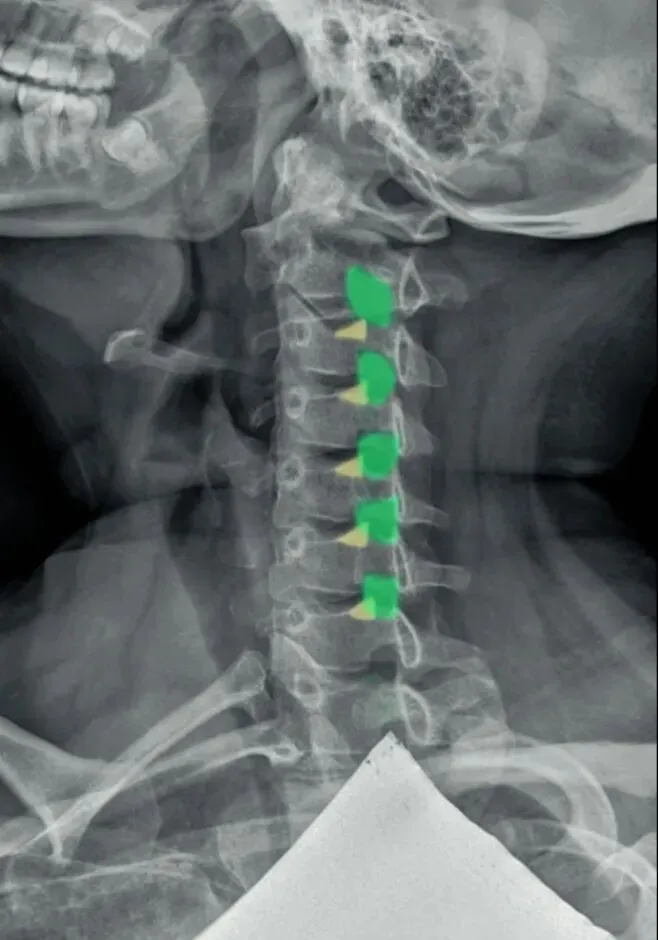

六旋指颈椎旋转,需结合颈椎正侧位观察。

颈椎正位主要观察棘突有没有偏歪,有没有在棘突中心轴线的连线上。

如果某一节椎骨的棘突中心点偏离,各棘突中心连线大于等于3毫米,则表示该节段颈椎有轴向旋转。

侧位主要观察椎体有没有双边征和关节突有没有双突征。

造成这两个征象的原因就是椎体后缘及双侧关节突没有完全重叠,摄影体位不标准时也会出现这种现象。所以我们要结合正侧位观察,如果正位没有出现某节段颈椎棘突偏移,但是侧位出现颈椎双凸或双边征时,大概率就是摄影体位不标准。反之正位能看到某节段颈椎棘突偏移,同时侧位能看到对应节段颈椎的双边或者双凸征时,基本可以确定椎体存在旋转。

七滑脱是指颈椎椎体的滑脱,以下位椎体分为四等份,以此判断上位椎体向前或者向后的滑脱程度,

也是我们所说的椎体序列不整齐,椎体后缘的平滑曲线出现台阶或错位,多发生在颈三和颈4椎体。

颈椎滑脱是颈椎不稳的结局,颈椎不稳多因椎间盘和关节突关节退变及关节活动度过多和过大所致。正常的颈椎侧位片只是能看到静态下的椎体滑脱,有的病人在做前屈和后伸活动时才出现滑脱,因此需做颈椎的过伸和过屈动力位侧位片检查来判断不稳。